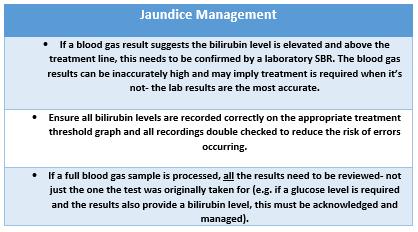

Fetal monitoring practice: Escalate – get support